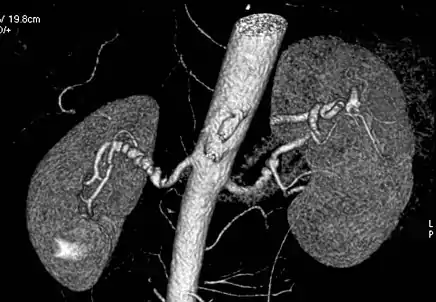

Renal arteries

Visualization of blood flow in the renal arteries (those supplying the kidneys) in patients with high blood pressure and those suspected of having kidney disorders can be performed using CTA. Stenosis (narrowing) of a renal artery is a cause of hypertension (high blood pressure) in some patients and can be corrected. A special computerized method of viewing the images makes renal CT angiography a very accurate examination.[5] CTA is also used in the assessment of native and transplant renal arteries.[2] While CTA is great for imaging of the kidneys, it lacks the ability to perform procedures at the same time. Thus traditional catheter angiography is used in cases of acute renal hemorrhage or acute arterial obstruction.[1]